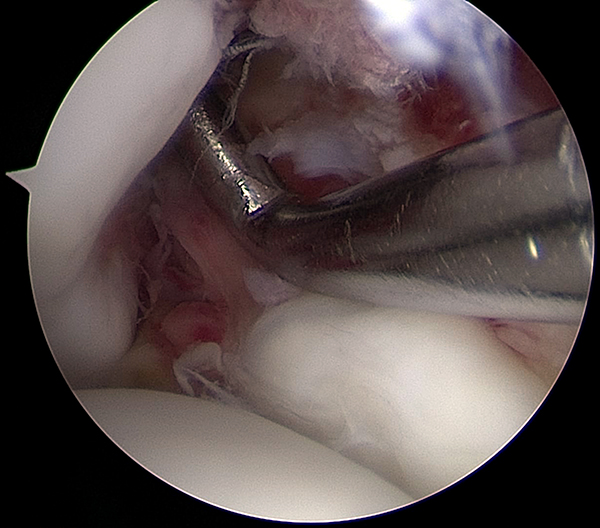

Todos fueron intervenidos quirúrgicamente por el mismo equipo quirúrgico con la metodología protocolizada que se realiza habitualmente en el centro. El procedimiento se realiza, con el paciente en decúbito dorsal, con anestesia raquídea, manguito hemostático colocado en la raíz del muslo, insuflado a 300 mmHg, lavado previo con clorhexidina y embrocado con alcohol ispropílico y clorhexidina. El primer tiempo es artroscópico, efectuado a través de los 2 portales clásicos antero-lateral y antero-medial, sin dispositivos de distracción. Se evalúa la articulación tibio-talar en busca de lesiones asociadas intra-articulares (fig. 1), y se evalúa la ruptura e inestabilidad de la sindesmosis (fig. 2). La diástasis se cuantifica en mm con el palpador (fig. 3). Se considera anormal un desplazamiento mayor a 2 mm. Se clasifica a la lesión como inestable cuando se logra ingresar con la óptica o con la punta del shaver en el espacio tibio-peróneo (abriendo la sindesmosis).

Figura 2: Medición de la lesión sindesmal con el palpador.